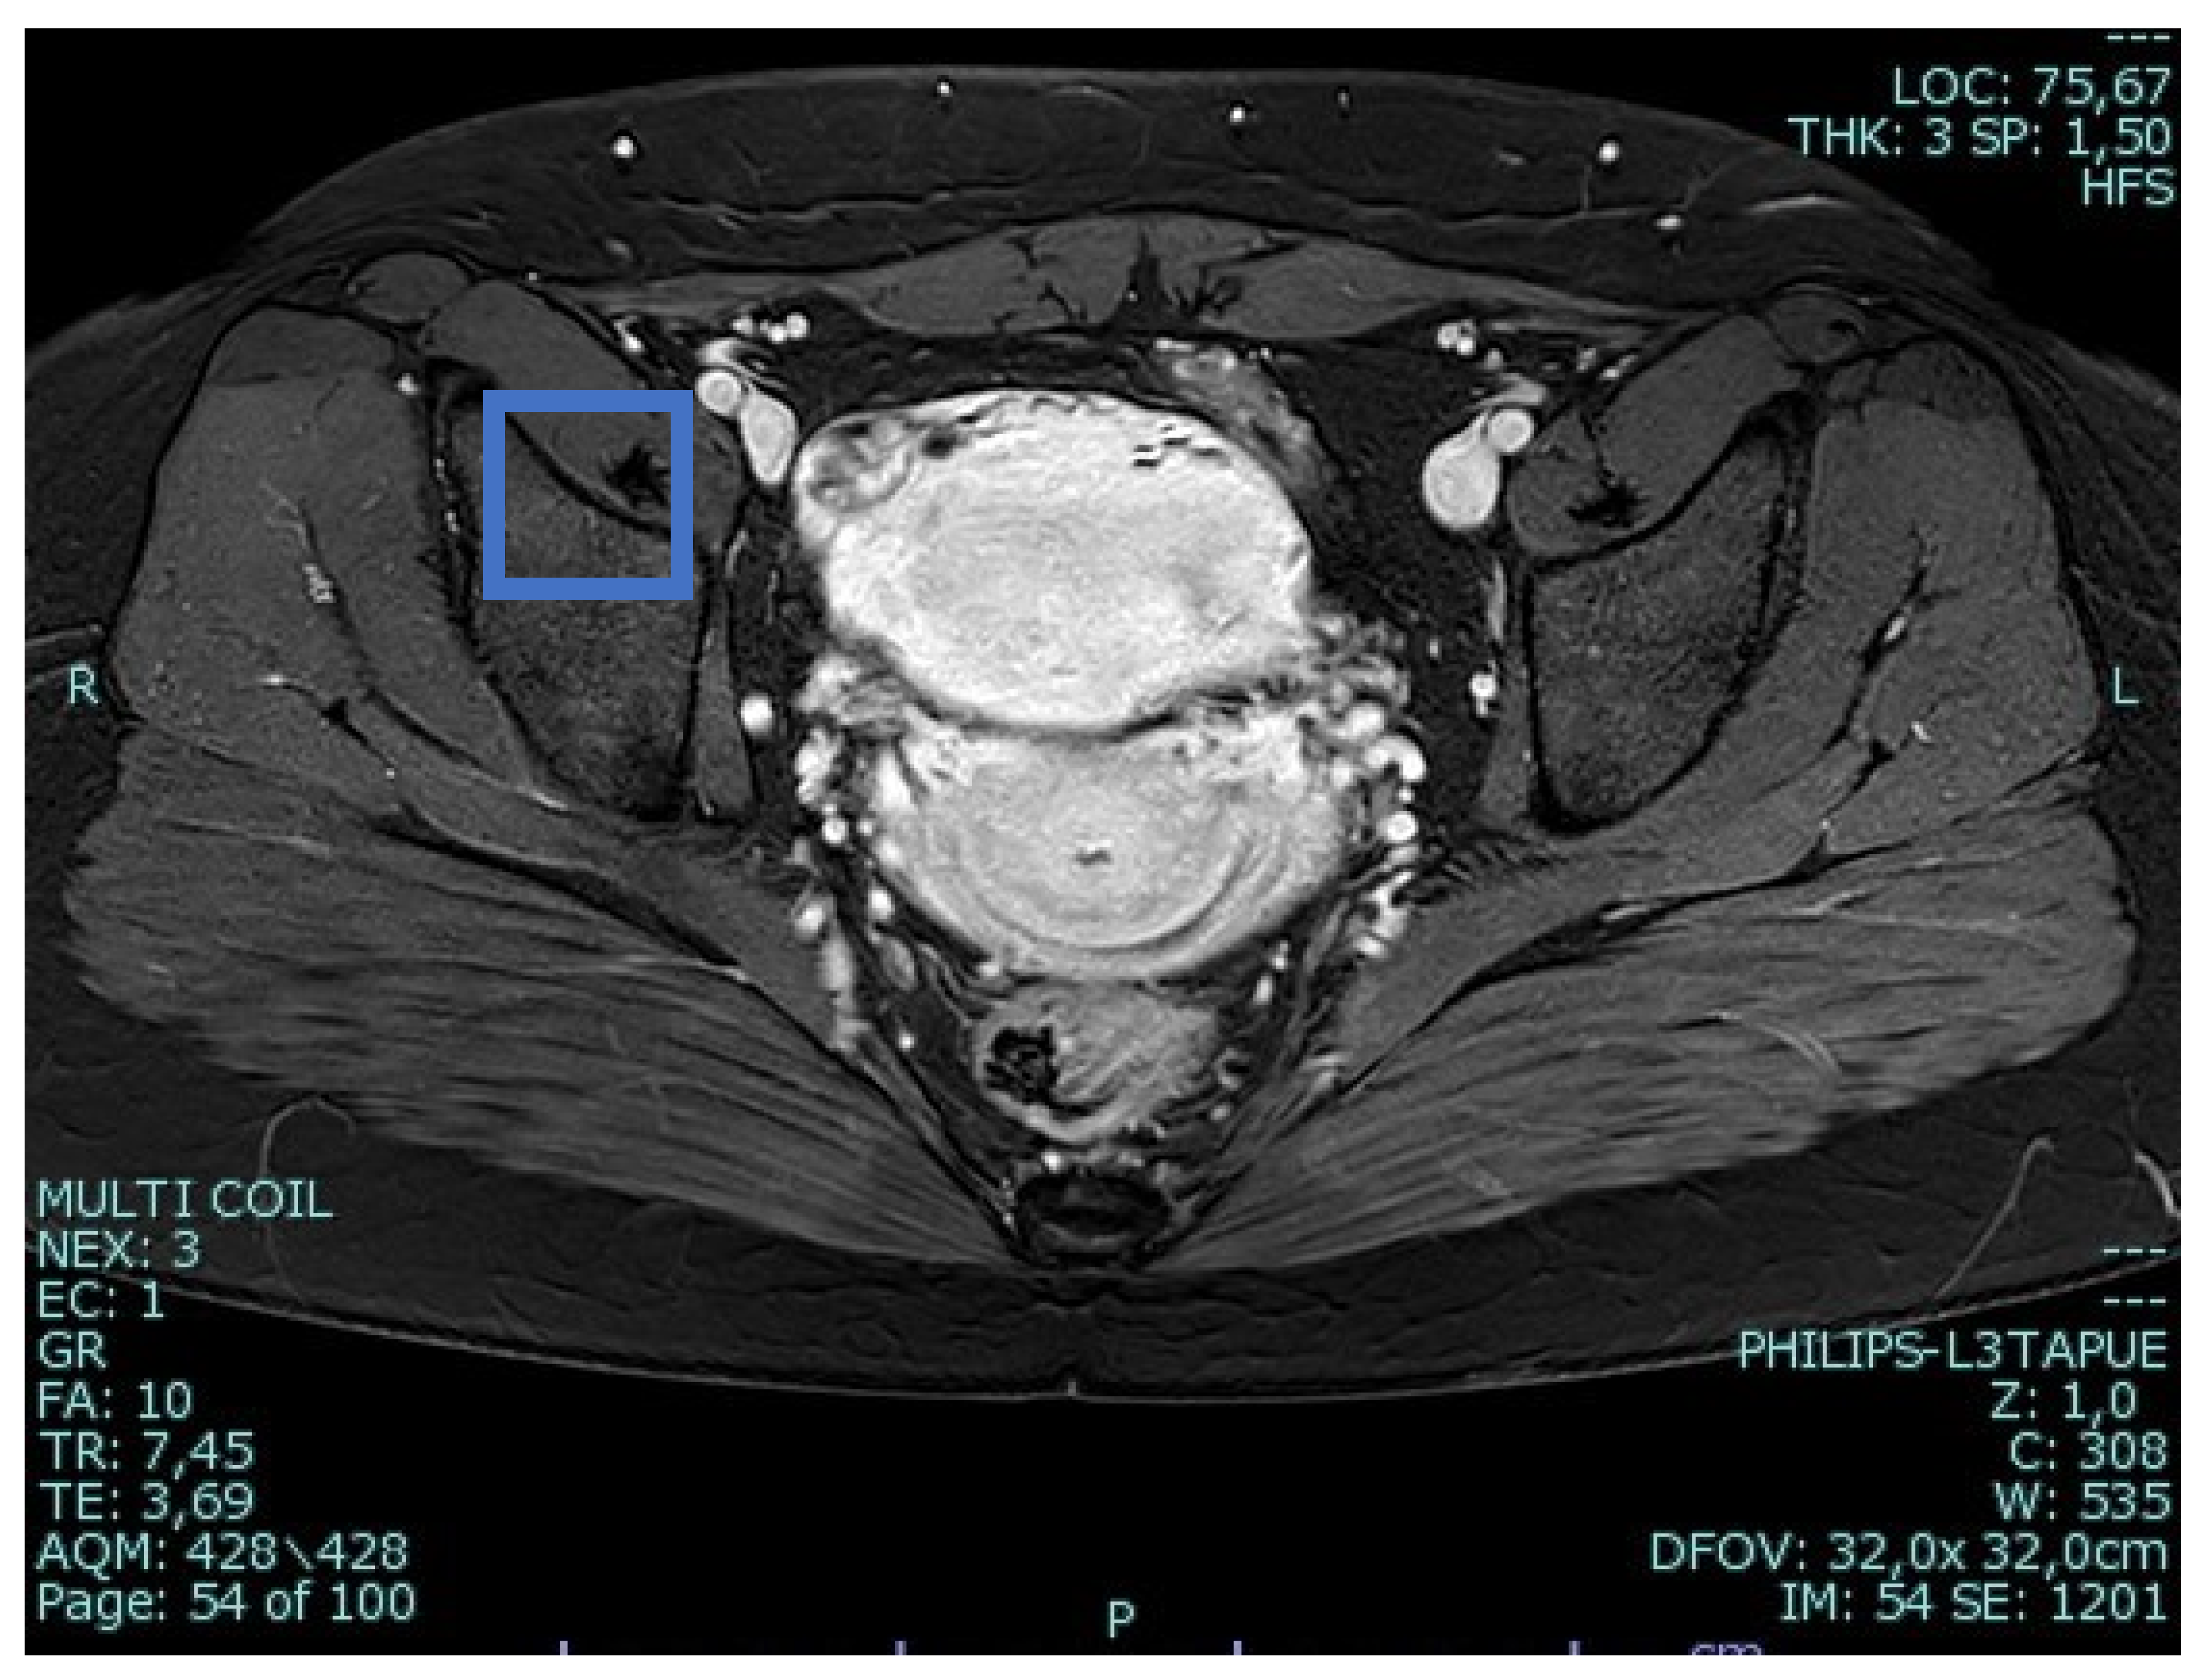

A 25-year-old woman, with a history of left tubal laparoscopic salpingectomy for an ectopic pregnancy, sought medical attention at the hospital’s emergency department after an episode of vaginal bleeding at 5 + 6 weeks of amenorrhea. At Day-1, her β-hCG was 2528 mUI/mL but a transvaginal ultrasound scan (TVUS) showed no clear evidence of pregnancy. Therefore, the patient was admitted with a diagnosis of pregnancy of unknown location (PUL). Upon admission, the patient was clinically and hemodynamically stable and did not report any pain or active bleeding. Serial measurement of her β-hCG in the following days was consistent with a suboptimal growth (3696 at Day-2, 5898 at Day-4, 10,984 at Day-7). Repeated TVUSs failed to show sure evidence of pregnancy until Day-7, when an intramural vascularized mass of 27 × 8 × 20 mm, with a gestational sac of 7 mm, a yolk sac and a 2 mm embryo with a heartbeat, was detected (Figure 1). Pelvic nuclear magnetic resonance (NMR) performed at Day-7 confirmed the presence of an intramyometrial T2-hypointense signal alteration of 20 mm in the right cornual area, surrounded by ectasic vessels, suggestive of interstitial pregnancy (Figure 2). After thorough counselling, a conservative management was proposed and accepted by the patient. The patient was administered a single oral dose of mifepristone 600 mg in combination with multidose systemic MTX 72 mg on days 0, 2, 4 and 6 from diagnosis. Follow-up by TVUS and β-hCG measurement was carried out. By Day-15, β-hCG reached a plateau and started reducing. A TVUS confirmed the termination of the pregnancy by involution of the gestational sac and the presence of the embryo with the disappearance of the fetal heartbeat. After 22 days from treatment, while the pregnancy was disappearing, in the same site, TVUS showed the appearance of a myometrial tubular hypoechoic region of 37 × 38 mm with an intensely vascular and multidirectional flow. Spectral Doppler ultrasound showed a low-resistance, high-velocity (peak systolic velocity of 128 cm/s) flow pattern, suggestive of uterine arteriovenous malformation (AVM) in the location of the previous interstitial pregnancy (Figure 3). The patient remained asymptomatic. To avoid menstrual bleeding and minimize the risk of metrorrhagia, a depot 3.75 mg shot of a GnRH analogue was administered every 28 days for 4 months. Considering the desire to preserve the fertility of the patient, the absence of guidelines for the treatment of AVM and the good results presented in the literature on uterine artery embolization as a conservative treatment, we performed a right uterine artery embolization, with sonographic resolution of the AVM within 3 months (Figure 4). We accessed the right common femoral artery and a 5-Fr introducing an angiographic sheath was placed. A 5-Fr Cobra catheter (Cook, Bloomington, IN, USA) was used to perform nonselective angiograms of the internal iliac arteries in order to achieve a general understanding of the vascular anatomy; the right internal iliac artery was selected after creating a Waltman loop with the Cobra catheter. The right uterine artery was selected using a microcatheter ranging from 2.0 to 2.4 Fr. As embolic materials, polyvinyl alcohol particles were used (Contour; Boston Scientific, Cork, Ireland). The rescue treatment had no complications. We present an unpublished case of interstitial pregnancy in a hemodynamically stable woman at an early gestational age successfully treated with medical therapy using MTX and mifepristone, who developed a peculiar complication.

Figure 2. Pelvic nuclear magnetic resonance confirming the presence of an intramyometrial T2-hypointense signal alteration of 20 mm in the right cornual area.